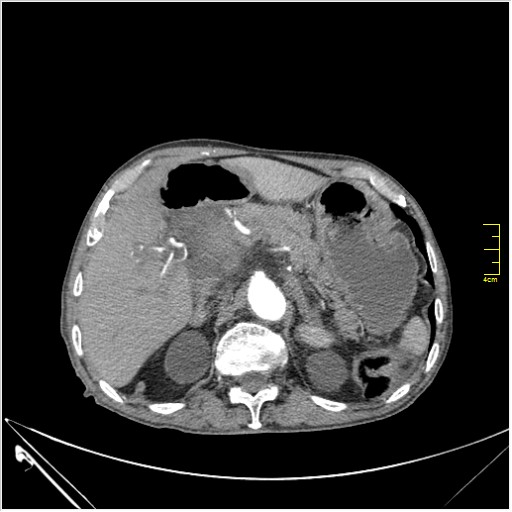

Пациент Т. 64 года, обратился на КТ брюшной полости амбулаторно (!), по направлению семейного врача с диагнозом abdominal mass, буквально: образование брюшной полости.

Huge abdominal aorta aneurism. Simple renal cortical cysts (Bosniak type 1).